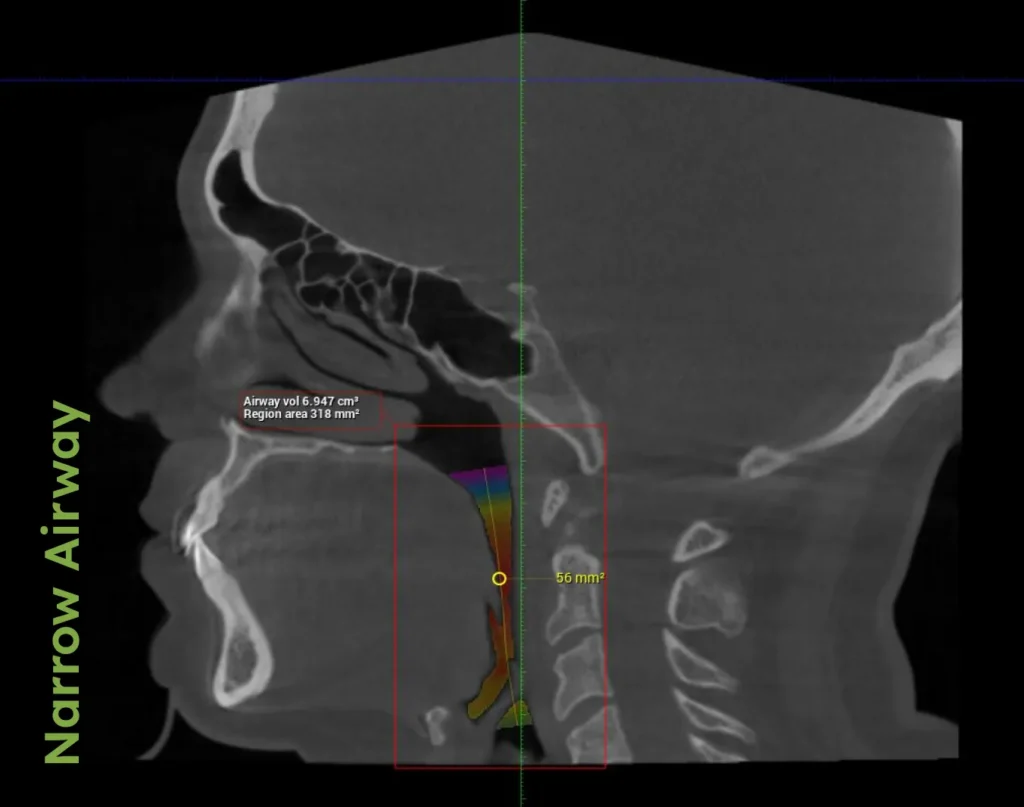

“We treat TMJD by addressing the primary culprit: a compromised airway. Our holistic approach integrates how the muscles, bite, posture, and respiratory conditions impact the jaw, creating personalized plans for a pain-free, healthier life,” explains Dr. Porter. He further emphasizes the necessity of understanding the interconnected nature of body systems, advocating for a treatment approach that considers overall physiological health to ensure the effectiveness of TMJD treatments.

Dr. Porter discusses in his book AIM the critical relationship between TMJD and airway health. A compromised airway can lead to dysfunctional jaw positioning, which stresses the temporomandibular joint and related muscles. This section details how enhanced airway health can alleviate TMJD symptoms, providing relief and preventing further complications.